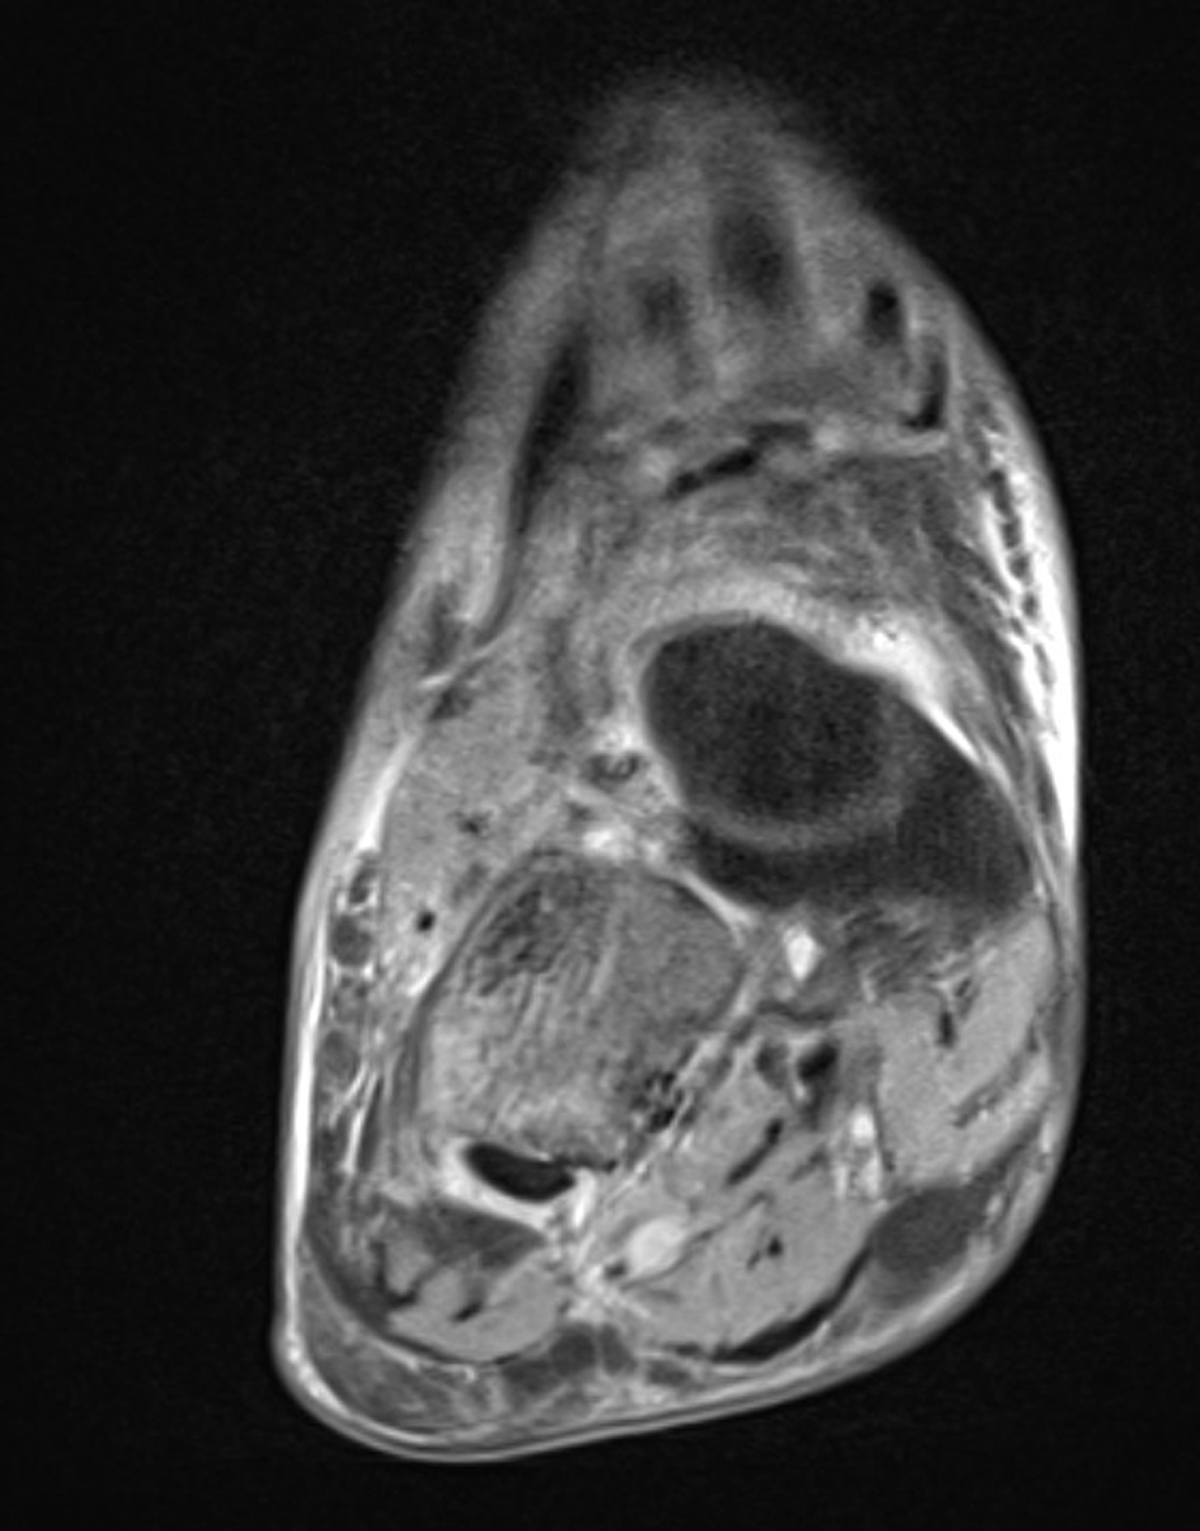

Figure 3

Quiz Case.